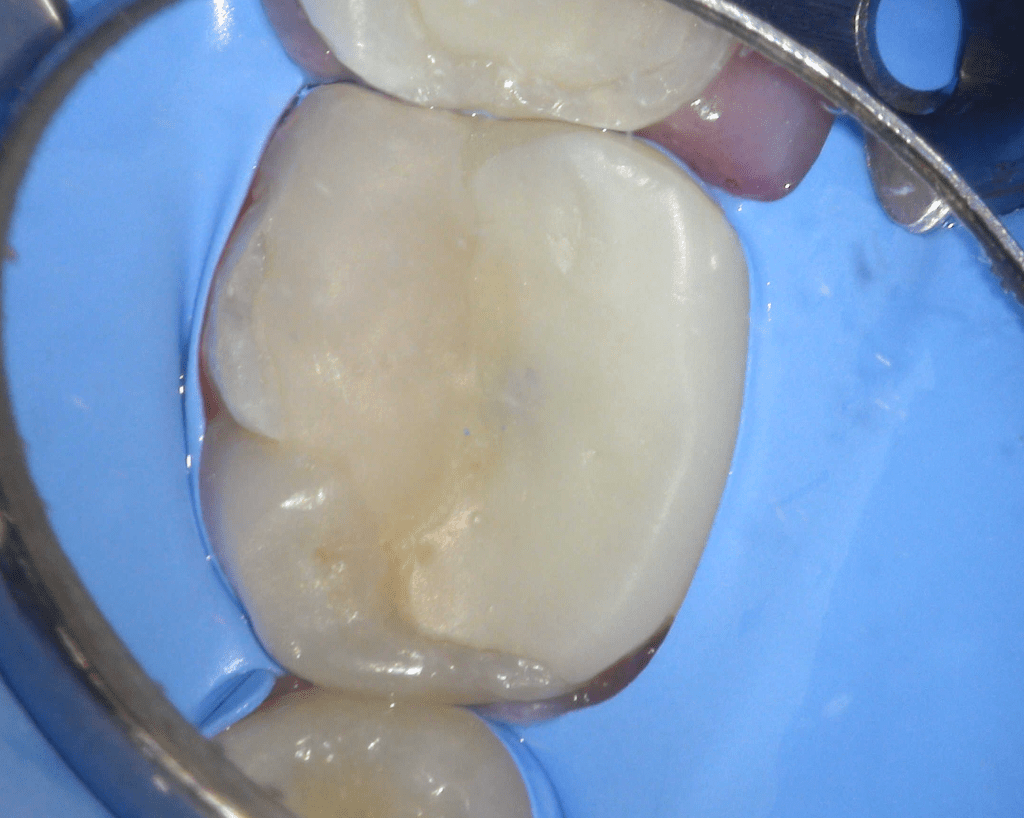

Reco preendo + 4 conductos molar superior